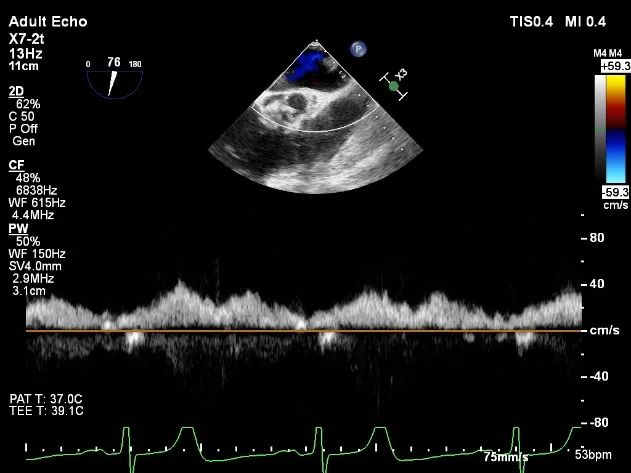

肺静脉收缩期反向血流

术后肺静脉频谱